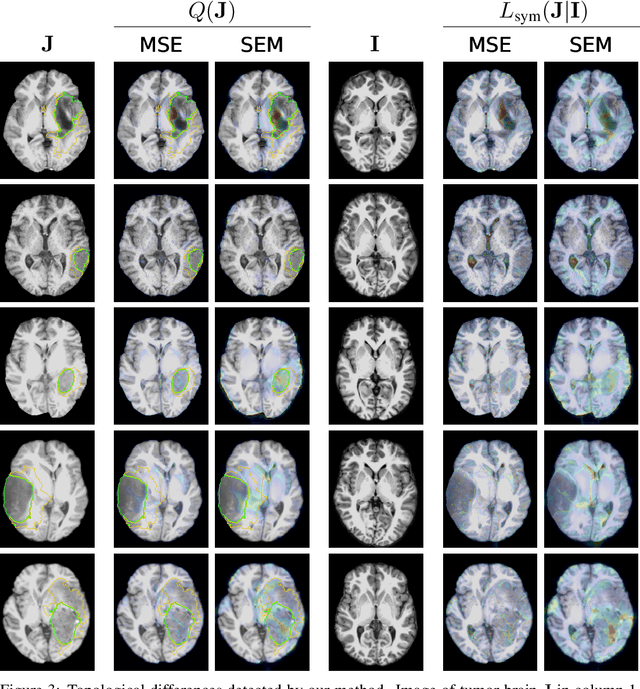

Abstract:Geometric alignment appears in a variety of applications, ranging from domain adaptation, optimal transport, and normalizing flows in machine learning; optical flow and learned augmentation in computer vision and deformable registration within biomedical imaging. A recurring challenge is the alignment of domains whose topology is not the same; a problem that is routinely ignored, potentially introducing bias in downstream analysis. As a first step towards solving such alignment problems, we propose an unsupervised topological difference detection algorithm. The model is based on a conditional variational auto-encoder and detects topological anomalies with regards to a reference alongside the registration step. We consider both a) topological changes in the image under spatial variation and b) unexpected transformations. Our approach is validated on a proxy task of unsupervised anomaly detection in images.